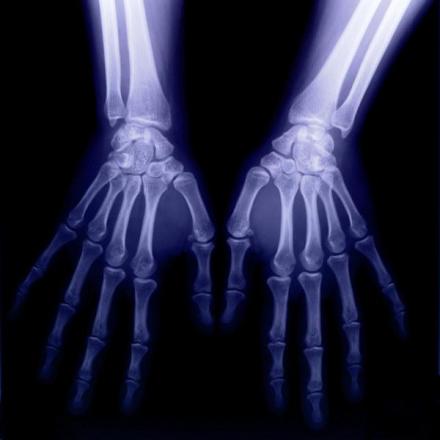

双手X光图片

X射线应用于医学诊断,主要依据X射线的穿透作用、差别吸收、感光作用和荧光作用。由于X射线穿过人体时,受到不同程度的吸收,如骨骼吸收的X射线量比肌肉吸收的量要多,那么通过人体后的X射线量就不一样,这样便携带了人体各部密度分布的信息,在荧光屏上或摄影胶片上引起的荧光作用或感光作用的强弱就有较大差别,因而在荧光屏上或摄影胶片上(经过显影、定影)将显示出不同密度的阴影。根据阴影浓淡的对比,结合临床表现、化验结果和病理诊断,即可判断人体某一部分是否正常 。

1、感光作用。X射线同可见光一样能使胶片感光。胶片感光的强弱与X射线量成正比,当X射线通过人体时,因人体各组织的密度不同,对X射线量的吸收不同,胶片上所获得的感光度不同,从而获得X射线的影像 。